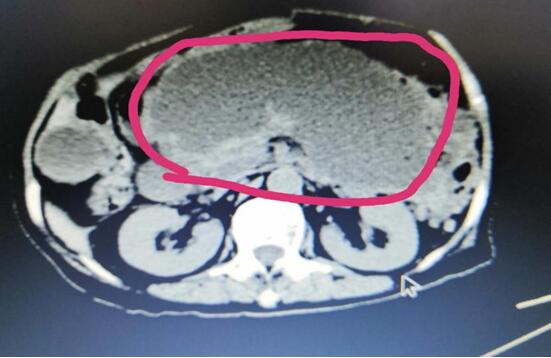

患者A,女,72歲,1年前因急性出血壞死性胰腺炎,曾行腹腔鏡下壞死胰腺組織清創(chuàng)+外引流術,術后出現(xiàn)急性胰腺假性囊腫,囊腫越來越增大,以至于病人不能做下蹲和彎腰動作,給生活造成極大不便。本次患者因急性腹痛入院,入院診斷為:胰腺巨大假性囊腫并發(fā)出血,重癥胰腺炎清創(chuàng)術后。

(術前腹部CT顯示胰腺巨大假性囊腫)